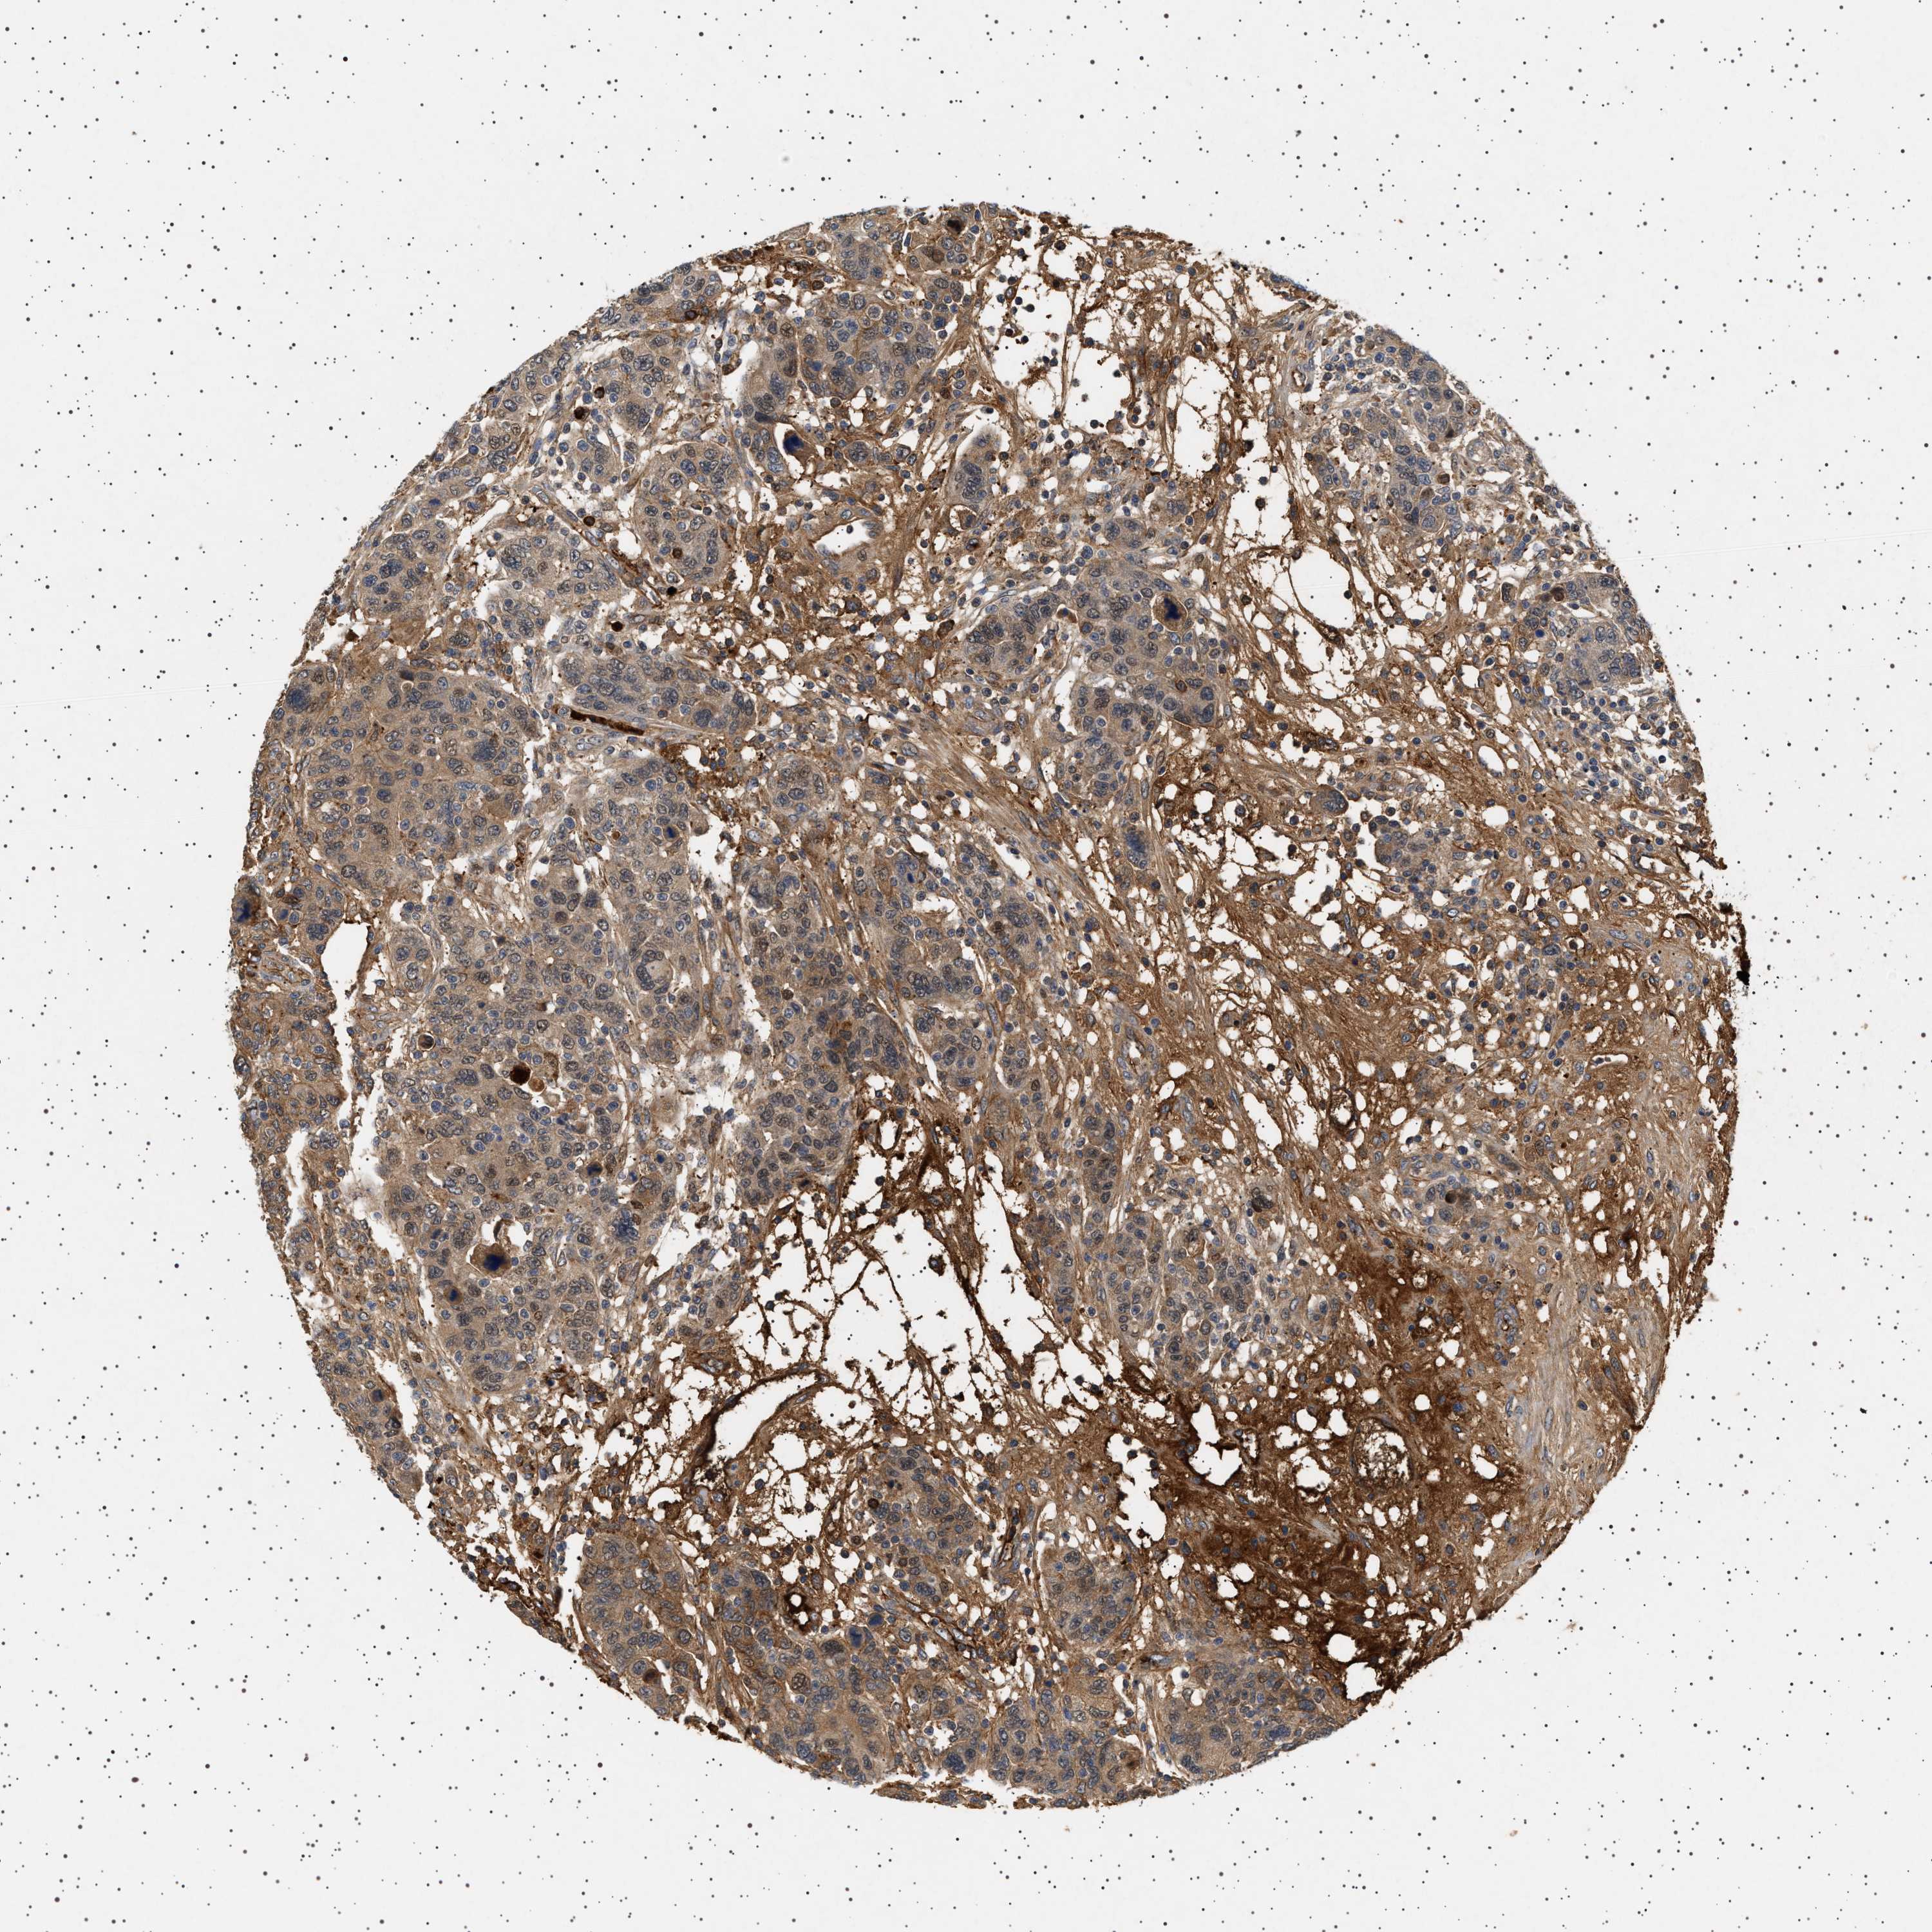

CANCER BREAST CANCER Show tissue menu

BRCA TCGA BRCA VALIDATION PROTEIN EXPRESSION